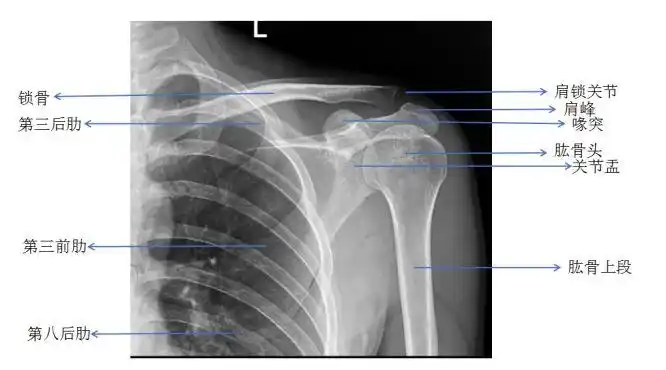

肩关节